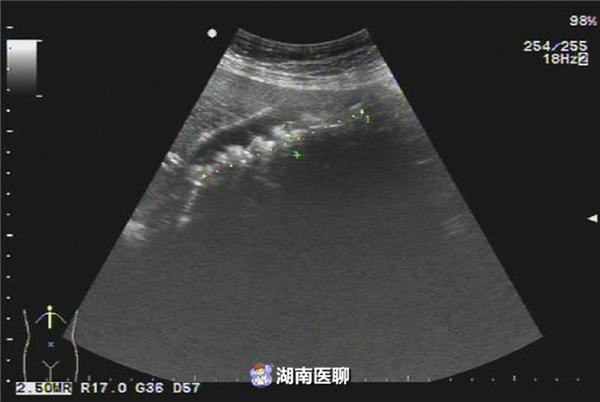

Hình ảnh siêu âm túi mật đầy sỏi của bệnh nhân.

Ngày 13/8, cô Lý bị đau ở phần bụng trên, mồ hôi túa ra ướt đẫm, khi cô được đưa vào bệnh viện địa phương, bác sĩ chẩn đoán tình trạng của cô là "túi mật bị viêm, kết sỏi túi mật ". Bác sĩ khuyên cô Lý nên tiến hành phẫu thuật cắt bỏ túi mật và lấy sỏi túi mật, nhưng cô Lý kiên quyết từ chối.

Ngày 16/8, cô Lý tiến hành phẫu thuật cắt túi mật nội soi tại bệnh viện Nhân Dân. Trải qua 1 tiếng đồng hồ, các bác sĩ đã thành công cắt bỏ túi mật, và kinh ngạc phát hiện có 258 viên sỏi túi mật hình vuông, có màu xanh nhạt.